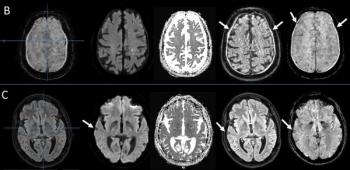

Noting a 7.4 percent incidence of motion artifacts on brain MRI scans for suspected stroke patients, the authors of a new study found that motion artifacts can reduce radiologist and AI accuracy for detecting hemorrhagic lesions.